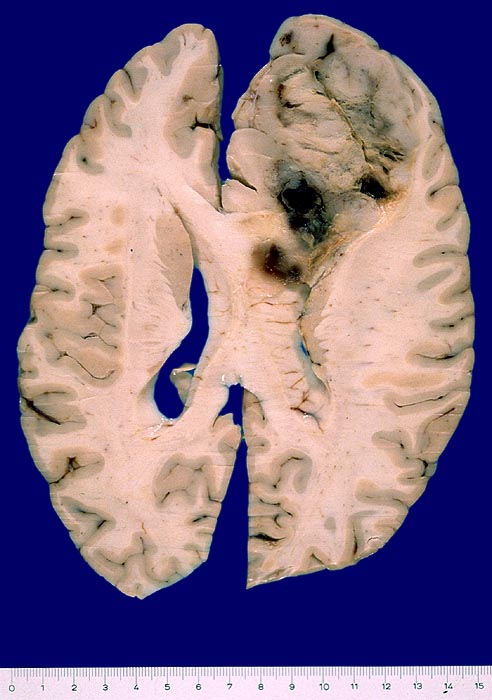

PathoPic ID 4035 - Oligodendrogliom

Oligodendrogliom

maligner Tumor

Hirn

Nervensystem

Grauer unscharf begrenzter Tumor frontal rechts mit fokalen Einblutungen.

Hirntumor frontal rechts. Keine Operation.

Makroskopie

24

männlich